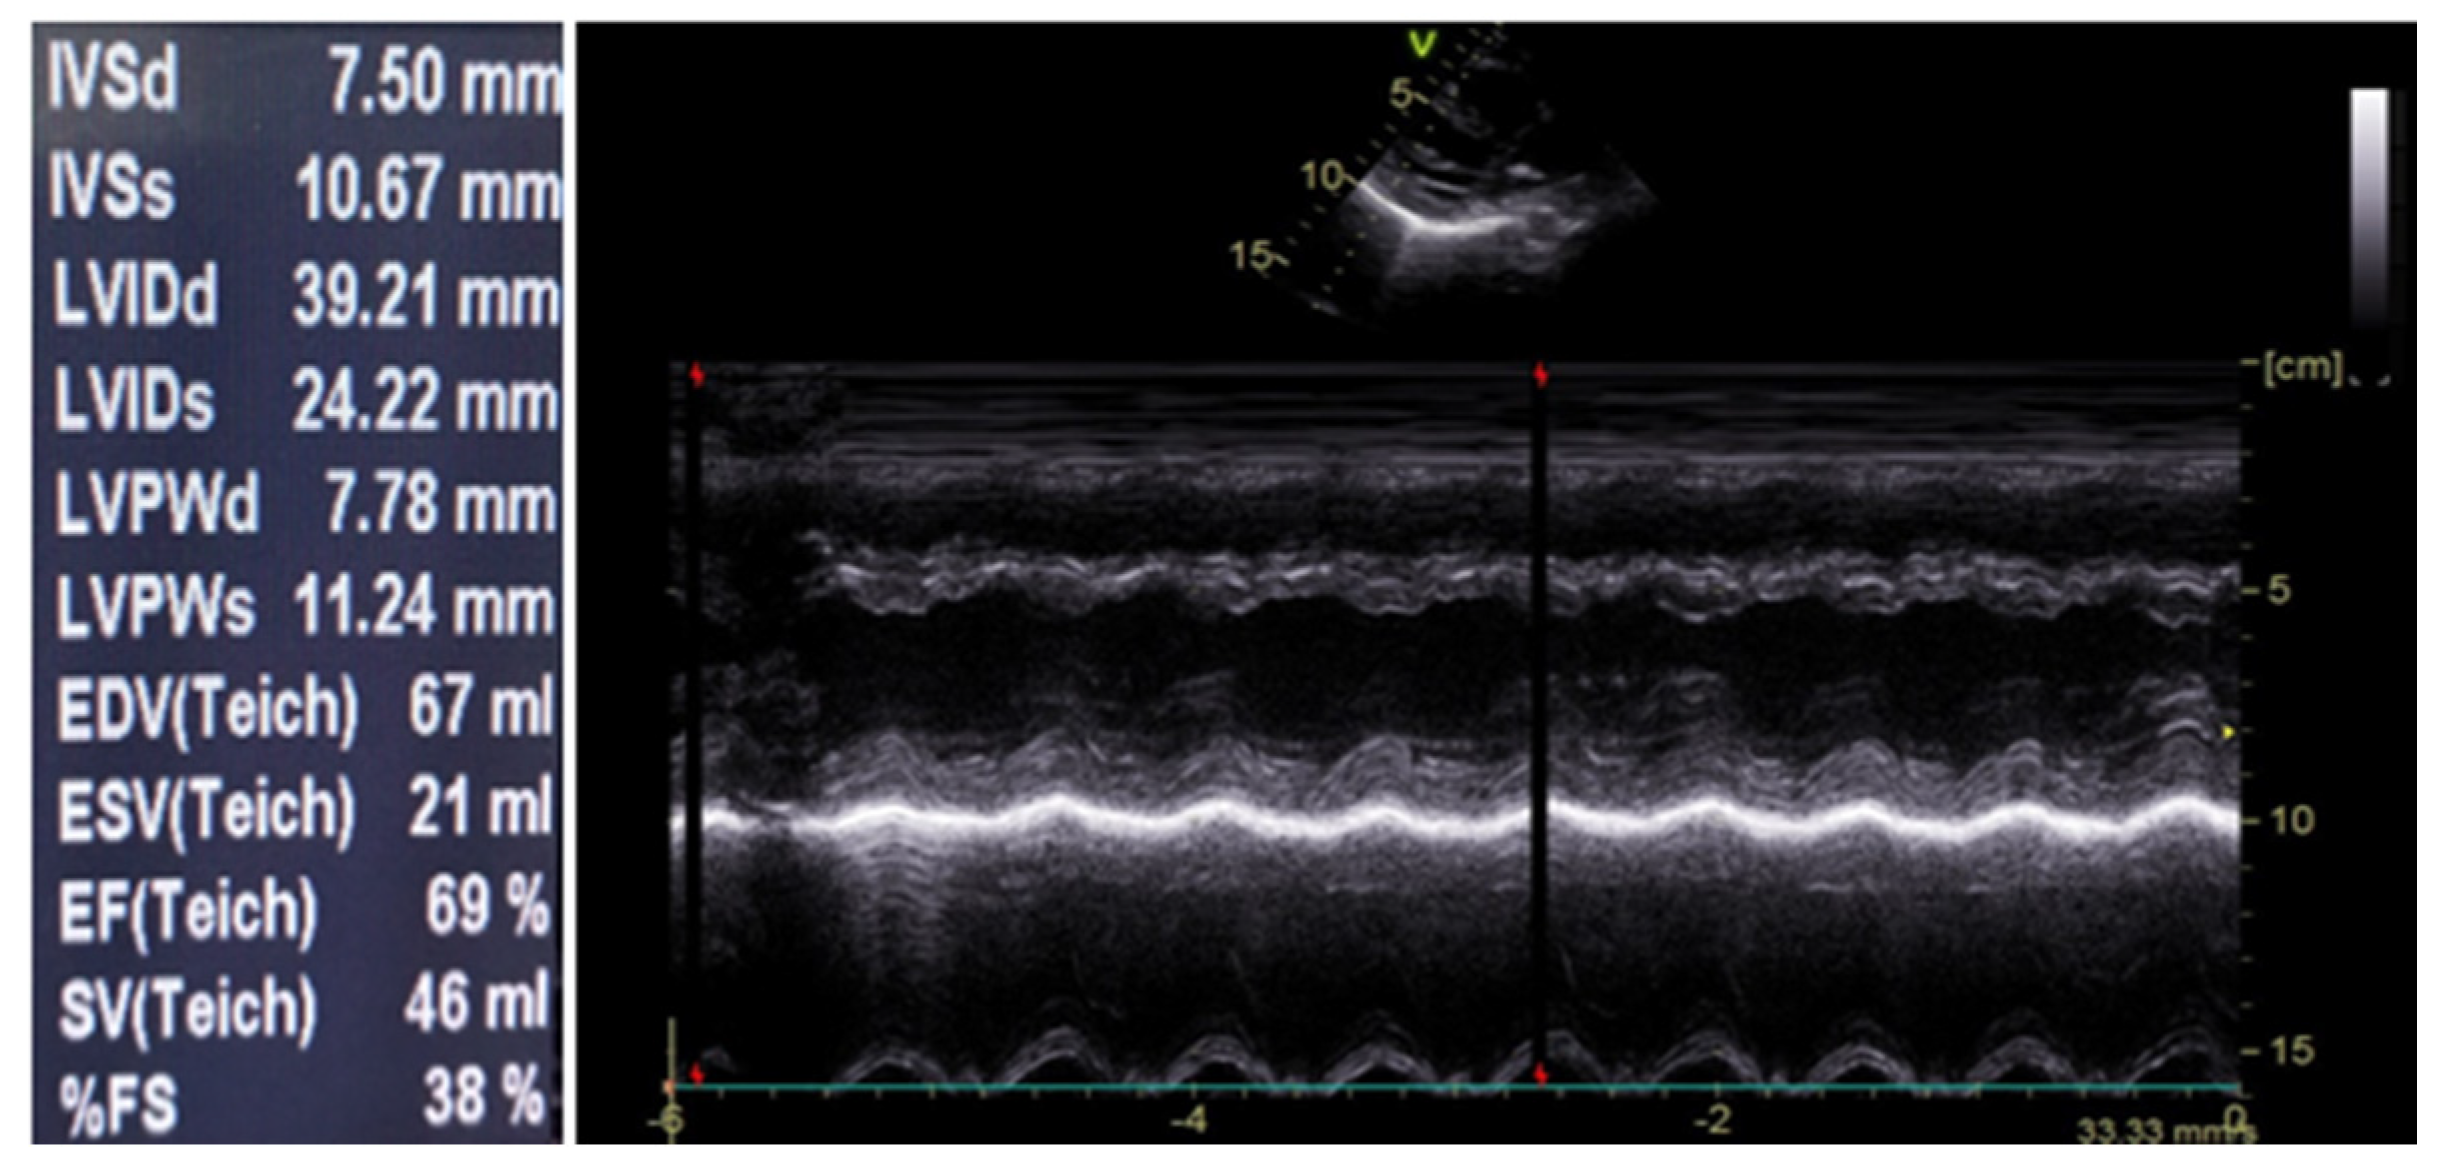

| Echocardiography | Normal | Normal | Normal | Normal | |||